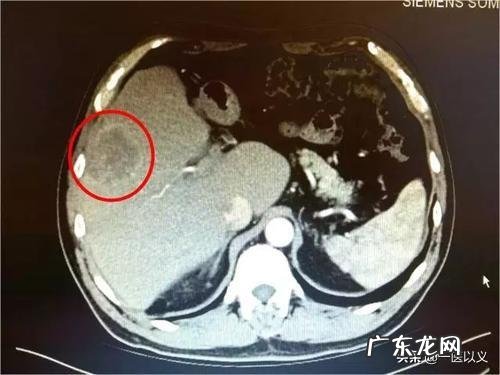

下面我给大家介绍一下做哪些检查可以发现早期肝癌一、肝脏彩超检查

1、首先 , 肝脏的彩超检查就可以发现早期肝癌 , 但是有人会有疑问 , 肝脏彩超挺便宜的 , 而且给出的报告就那两幅图 , 是不是很难发现早期肝癌啊 。对于这样的疑问 , 我想告诉你们 , 千万不要小瞧个肝脏的彩超 , 这有时候可比肝脏的CT或磁共振还厉害呢 。肝脏的彩超可以明确的区分液态与固态 , 可以分出不同密度的肝组织 , 也可以分清肝血流与胆管 。是不是有点摸不到头脑?崔医生给你细细道来 。

2、肝癌一般情况是都是与正常的肝脏组织时不同的密度的 , 多成单发结节样改变 , 周围还有被膜 , 这些都是肝癌的特点 , 而彩超是可以抓住这些肝癌的特点的 , 就好比说你的相亲对象告诉你她穿什么样的衣服 , 身高有多少、戴没戴眼镜 , 而你就可以根据这些特征特征在电影院门口认出她一样 。

3、当然肝脏的肿瘤并不一定都是肝癌 , 也有许多是良性的肿瘤 , 如肝血管瘤、肝囊肿等 , 你是不是以为肝脏彩超会区分不出呢?那你就大错特错了 , 肝脏彩超可以轻松的分辨出这些肿瘤 , 因为每种肿瘤在彩超下的表现都是不一样的 , 当然也存在不能区分的情况 , 如肝硬化患者发现肝脏的结节样改变 , 彩超就可能分辨不出来是早期肝癌还是肝硬化结节 。

4、肝脏彩超一般可以发现1cm以上的肝癌 , 但是依据不同的彩超机型还有不同水平的彩超医生 , 有的医院可以发现0.5cm以上的肝癌 , 而有的医院却不能达到这样的水平 , 因此 , 如果你想用肝脏彩超来筛查是否有早期肝癌的存在 , 我建议你要去大一点的医院 , 不是我吹捧大医院的彩超水平 , 但是一般情况下来说 , 相对水平会高一点 , 这也是在临床工作中发现的 , 有一些肝癌患者3个月前在当地查的肝脏彩超没有发现肝脏的异常 , 但是患者来这个医院看病时 , 做检查发现肝癌已经有2cm以上了 , 当然我承认有些地方医院的超声医生水平比大医院还厉害 。